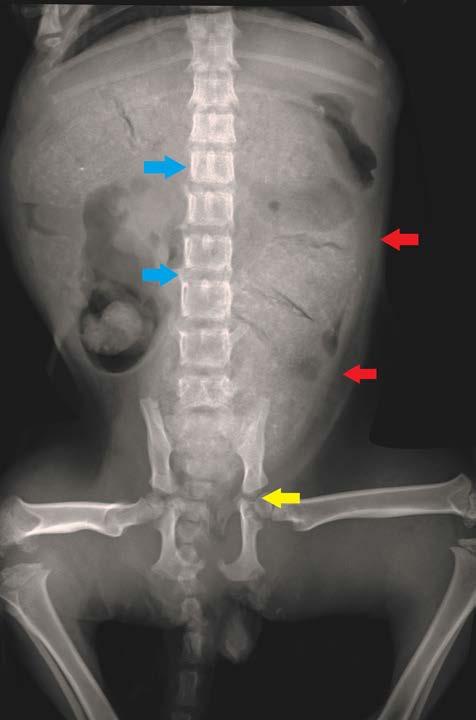

Las cepas de CPV-2 y FPV pueden infectar otros hospedadores (coyotes, lobos, mapaches, panda rojo, hurones, leones, chacales y mangostas)6,10-13 y per manecer en el ambiente más de un año.5,14 El CPV se propaga rápidamente por ruta fecal-oral (transmisión directa) o por exposición oronasal a fómites contami nados con heces (transmisión indirecta). Se replica en la orofaringe, ganglios mesentéricos y timo, pro duciendo viremia 1-5 días tras la exposición. Poste riormente, infecta a las células en rápida división de las criptas del epitelio intestinal, médula ósea, lengua, cavidad oral y miocitos, y otros tejidos (pulmones, hí gado, bazo y riñones) (Fig. 1). El periodo de incuba ción comprende entre 4 y 14 días, precediendo la elimi nación de virus en heces a la sintomatología clínica en el paciente.1,4-6 Durante el destete, los enterocitos de las criptas intestinales tienen un alto índice mitótico debi do a los cambios en la flora bacteriana y la dieta, por lo que son más susceptibles al tropismo vírico.1,2,4-6,15

El CPV interrumpe el recambio normal celular del intestino delgado, produciendo acortamiento y atro fia de vellosidades, que pierden la capacidad de ab sorción, causando enteritis profunda, con vómitos, diarreas hemorrágicas (Fig. 2), malabsorción y trans locación bacteriana por ruptura de la integridad de la barrera intestinal (aumenta el riesgo de septicemia por E. coli).1,2,4-6,15 Otros signos clínicos son anorexia, depre sión, fiebre, pérdida de peso y deshidratación.

Figura 1. del parvovirus canino. Figura 2. Diarrea hemorrágica en un paciente canino con parvovirus.

Fisiopatología

yMantenimientocirculaciónde virus Otros órganos: - Corazón - Hígado - Riñones - Pulmones - Cerebro Eliminaciónvirusenheces (3 días post-infección4 semanas) sanguinolentaDiarreaNecrosisvellosidadesintestinales intestinalEpitelio Viremiaensangre Replicación viral en médula ósea1-5 días post-infección Infecciónoral Replicación viral en tejido linfoide (orofaringe mesentéricos,timo)